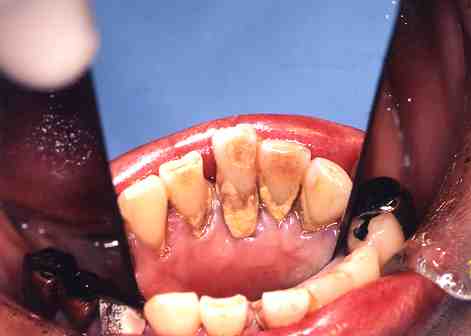

(6)歯石除去

1.歯の裏側に歯石が

いっぱいついています。